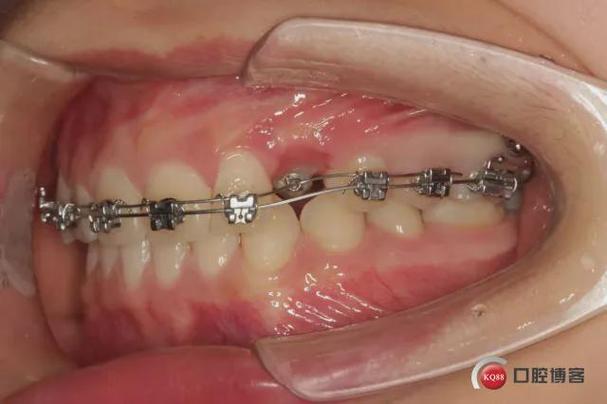

闭合牵引(针对部分萌出尖牙)

- 粘接附件:在已萌出的尖牙牙面粘接托槽,弯制圆丝或镍钛丝作为主弓丝,将尖牙纳入弓丝系统。

- 牵引方式选择:

- 颌内牵引:用弹性链或螺旋弹簧连接尖牙托槽与磨牙带环,利用磨牙作为支抗;

- 颌外牵引:通过头帽与口外弓装置,增强支抗力量,适用于严重倾斜的尖牙;

- 微种植体支抗牵引:在尖牙与磨牙之间植入微种植体,用拉簧直接牵引,效率高且支抗稳定。

- 动态调整:牵引过程中需密切监控尖牙移动速度(理想速度为1mm/月),若出现移动停滞,需检查牵引力是否充足、附件是否脱落,或通过CBCT排查骨性阻力。